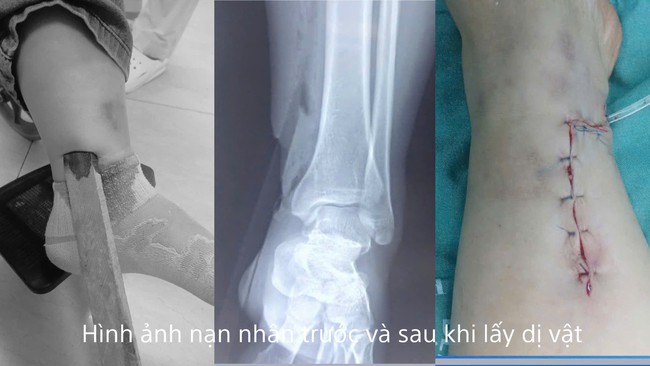

Hình ảnh dị vật là thanh gỗ cắm sâu vào cẳng chân người bệnh và sau phẫu thuật. Ảnh: BVCC

Theo thông tin từ Bệnh viện Kiến An, bệnh nhân Đỗ Thị Th. (trú tại phường Phù Liễn, thành phố Hải Phòng) được đưa vào cấp cứu trong tình trạng vết thương hở phức tạp, dị vật là thanh gỗ cắm sâu vào cẳng chân.

Ca phẫu thuật diễn ra an toàn, dị vật được lấy ra thành công.